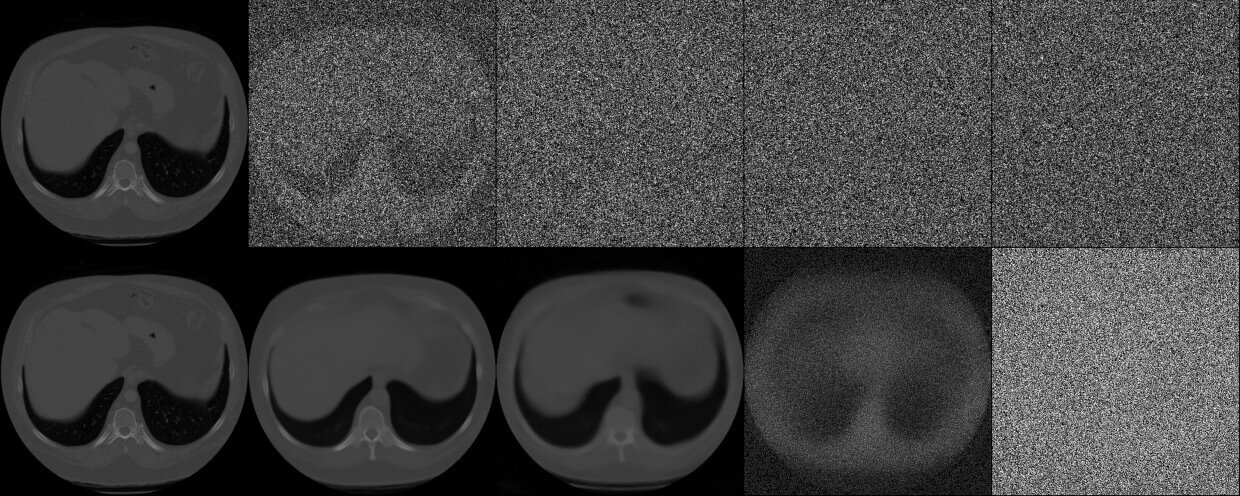

\(\hat{l}_{\alpha}\)

\(\hat{u}_{\alpha}\)

\(\hat{u}_{\alpha} - \hat{l}_{\alpha}\)